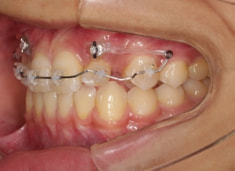

治療開始時

検査時のレントゲン分析では、上下顎の関係は、上顎の劣成長があり下顎前突傾向という値がでておりましたが、前歯ジャンプ後はフェイスマスクの効果もあり、上下顎の関係は正常化しています。

上顎が若干優位になっていますので、今後の下顎の成長のための貯金になっているくらいです。